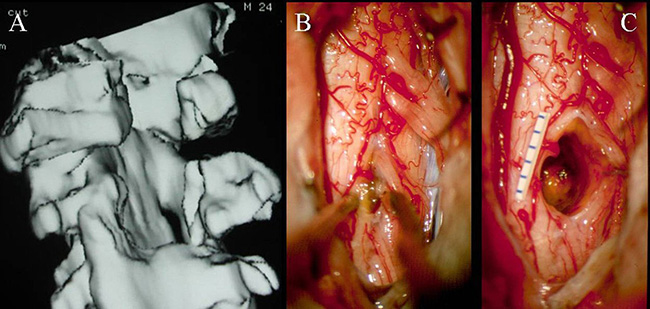

半椎板切除术是于1992年最初为世界颅底脑干肿瘤手术大师德国巴特朗菲教授提出的、用于治疗脊柱内部出现的髓外病变。后为了尽可能地实现微创手术,巴特朗菲教授团队使用半椎板切除术作为髓内海绵状血管瘤的一种方法。

半椎板切除术主要根据髓内海绵状血管瘤的定位选择患者位置,患者在俯卧位进行手术。医生在病变区域通过标准方法,即通过背根入口区或中线脊髓切开术接近深部病变。除了精确的定位和脊髓的极佳进入区域,解剖技术可能会影响髓内海绵状血管瘤的手术结果。手术过程中,使用双极钳和微型剪刀来断开引流血管是非常的重要。在确定手术平面后,应以锋利的解剖方式进行病灶表面周围的解剖,以避免正常脊髓组织的损伤。

(A-C)3D-CT扫描显示位于C1-2水平的髓内CM的术后图像。(B)在术中脊髓表面观察到含铁血黄素染色。(C)完全切除髓内CM,显示髓鞘切开的程度

巴特朗菲教授指出,显微镜可用来安全地进行髓内手术切除,当创口最小化并且在精确的肿瘤位置进行切除时,这些损伤通常不会在切除期间出血。术中神经监测对神经外科医生有很大帮助,使其能够更精确地操作并且术后神经功能缺损的风险更低。由于髓内海绵状血管瘤通常位于脊髓的背面,因此,我们证明术中SSEP监测是监测此病手术中脊髓完整性的可靠手段。